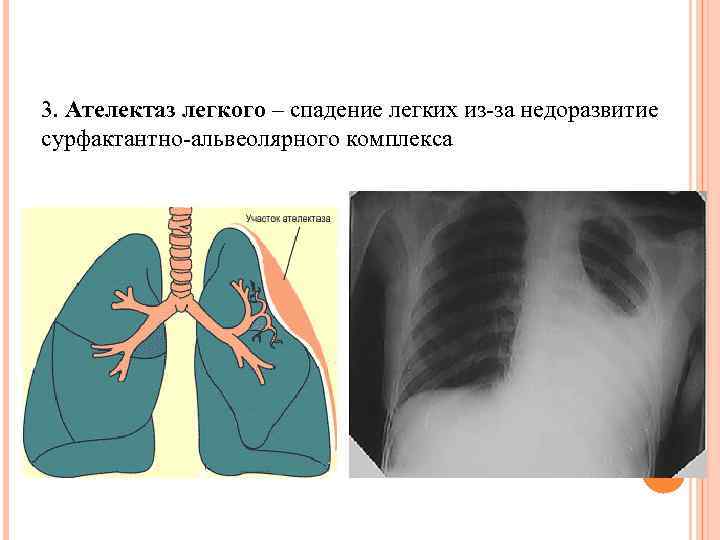

3. Ателектаз легкого – спадение легких из-за недоразвитие сурфактантно-альвеолярного комплекса

3. Ателектаз легкого – спадение легких из-за недоразвитие сурфактантно-альвеолярного комплекса